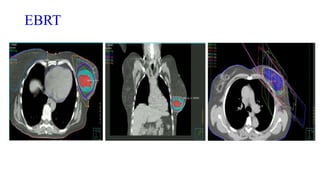

2) External beam (EBRT)

EBRT